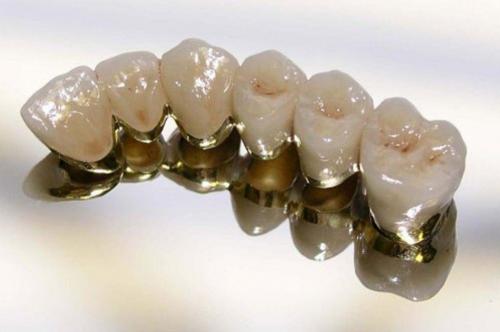

Металлокерамические протезы являются самым востребованным материалом для восстановления зубов коронкой или мостом. Это эстетичный и прочный вид протеза, который имеет привлекательную стоимость. У металлокерамики есть недостатки, однако, в современной стоматологии можно найти адекватное решение, которое устранит минусы конструкции. О чем стоит знать пациентам, решившимся на установку металлокерамики?

Металлокерамика прочная

Сплав кобальта и хрома имеет хорошую биосовместимость и высокие показатели прочности. Никель-хромовые сплавы более пластичные, но по прочности уступают. Титан кроме высоких показателей прочности и износостойкости еще и биоинертный металл. Сплавы драгоценных металлов прочные, биоинертные, придают зубам светлый теплый оттенок, что делает коронку эстетичнее. По прочности и долговечности титан и сплавы на основе золота прочнее, служат дольше, благодаря хорошей биосовместимости.

Металлокерамика долго служит

Срок службы металлокерамических коронок составляет от 5 до 12 лет. При соблюдении гигиены, правильной установке коронки и отсутствии врачебных ошибок на этапе изготовления и подгонки. Если у пациента зубной мост с опорой на собственные зубы, то следует помнить о факторах, сокращающих продолжительность службы металлокерамики. К ним относят: